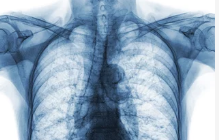

2. 어깨 석회질 치료 방법: 비수술적 치료

대부분의 어깨 석회질은 비수술적 치료로 증상을 완화할 수 있습니다. 초기 치료는 통증 완화와 염증 억제를 목표로 진행됩니다.

- 물리치료:

- 온찜질이나 냉찜질로 통증 완화

- 초음파 치료 및 레이저 치료로 염증 감소